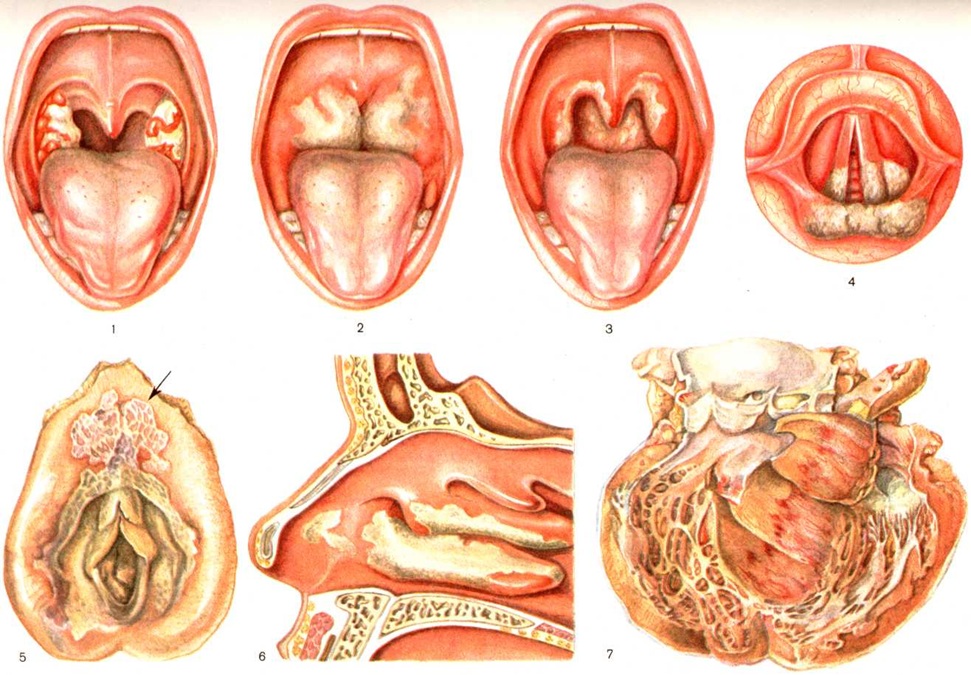

Дифтерия зева — наиболее частая форма; она наблюдается в 85—90% и более всех случаев Дифтерия. Различают три основные формы: локализованную, распространённую и токсическую.

Локализованная форма характеризуется образованием на миндалинах типичных налётов в виде белых и серовато-белых наложений с гладкой поверхностью, чётко очерченными краями; они плотно сидят на подлежащей ткани и не снимаются тампоном, за пределы миндалин не переходят (цветной рисунок 1). Слизистая оболочка зева умеренно гиперемирована. Боль при глотании умеренная или слабо выраженная. Иногда налёты имеют вид небольших бляшек, располагающихся преимущественно в лакунах миндалин (островчатая форма). Регионарные (верхнешейные) лимфатический, узлы умеренно увеличены и болезненны при ощупывании. Интоксикация выражена относительно слабо, она проявляется лишь умеренным повышением температуры, некоторым расстройством самочувствия, плохим аппетитом, слабостью, умеренной тахикардией.

Распространённая форма проявляется налётами, распространяющимися за пределы миндалин — на слизистую оболочку нёбных дужек, язычка, а иногда всей нёбной занавески (цветной рисунок 2). Умеренная боль при глотании. Реакция со стороны регионарных лимфатический, узлов примерно такая же, как и при локализованной форме; их припухлость и болезненность могут быть более выраженными. Более выражены и явления общей интоксикации: температура повышается до 38—39°, общая разбитость, слабость, анорексия, головные боли, расстройство сна, иногда вначале наблюдается рвота.

Токсическая форма (токсическая Дифтерия) в большинстве случаев начинается бурно: температура поднимается до 39° и выше, появляются головные боли, выраженная слабость, расстройство сна, анорексия, иногда рвота и боль в животе. Изредка отмечаются явления возбуждения или выраженная вялость, адинамия. Иногда при наличии тяжёлого процесса в зеве общие клин, проявления интоксикации выражены умеренно, самочувствие нарушается относительно мало. Умеренная боль при глотании. В зеве — распространённые налёты. На 2—3-й день болезни поражение зева принимает весьма характерный вид: слизистая оболочка мягкого неба, глотки отёчна, но гиперемирована относительно слабо; миндалины резко увеличены и нередко почти соприкасаются друг с другом; их поверхность выстлана толстыми бугристыми налётами белого и грязно-белого цвета, распространяющимися на мягкое и твёрдое небо (цветной рисунок 3). Язык обложен, губы сухие, потрескавшиеся. Из зева ощущается специфический неприятный сладковато-гнилостный запах. Иногда процесс распространяется на носовую часть глотки и полость носа; появляются обильные серозные, серозно-кровянистые выделения из носа. Кожа около носовых отверстий и на верхней губе экскориируется. Одновременно с развитием процесса в зеве или несколько позже в области верхне-шейных лимфатический, узлов появляется болезненный инфильтрат плотноватой консистенции с расплывчатыми контурами. Над поражёнными лимфатический, узлами и в их окружении на большем или меньшем протяжении мягкие ткани (подкожная клетчатка) отёчны (рисунок 4). Кожные покровы над отёчными тканями сохраняют нормальную окраску. Надавливание в области отёка безболезненно и не оставляет ямок; при толчкообразном ударе пальцем ткани сотрясаются наподобие желе или студня (симптом «желе», описанный С. Дифтерия Носовым в 1957 год). Распространённость отёка подкожной клетчатки соответствует выраженности интоксикации, поэтому ею руководствуются для разделения токсической дифтерии на три степени: I степень — распространение отёка до середины шеи, II степень — до ключицы, III степень — ниже ключицы. В первые дни болезни глубокая интоксикация у значительной части больных не проявляется. Отмечаются тахикардия, повышенная возбудимость сердца и обычно несколько повышенное АД Различные тяжёлые последствия интоксикации (резко выраженные расстройства со стороны нервной и сердечно-сосудистой систем) развиваются к концу первой или, чаще, на 2-й недель и позже.

При меньшей выраженности описанных симптомов выделяют субтоксическую форму Дифтерия зева, при которой нет отёка шейной клетчатки, а отмечается только пастозность тканей в области шейных лимфатический, узлов. Интоксикация при ней менее выражена, токсические осложнения наблюдаются значительно реже.

Другие варианты токсической формы Дифтерия зева редки, отличаются особой злокачественностью. При гипертоксической форме, помимо бурно прогрессирующего местного процесса, свойственного токсической форме, наблюдается тягчайшая интоксикация (смотри полный свод знаний) с катастрофически нарастающим упадком сердечно-сосудистой деятельности. Больные обычно погибают в первые 3—5 дней от начала болезни. Геморрагическая форма характеризуется симптомокомплексом токсической Дифтерия II — III степени в сочетании с явлениями геморрагического диатеза (смотри полный свод знаний Геморрагические диатезы). Летальность при этой форме очень высокая.

В части случаев поражение гортани развивается либо одновременно, либо вслед за Дифтерия зева или носа (вторичный круп, комбинированная форма). Процесс локализуется на слизистой оболочке гортани или гортани и трахеи. Если он распространяется в бронхи, возникает тягчайшая форма Дифтерия— распространённый (нисходящий) круп. Болезнь начинается с умеренного повышения температуры, нарастающей охриплости голоса, грубого лающего кашля, вскоре теряющего свою звучность и становящегося хриплым. Обнаруживается гиперемия и отёчность слизистой оболочки гортани; налёты могут ещё отсутствовать. Начальная стадия болезни называется дисфонической, катаральной или стадией крупозного кашля, продолжается в среднем около суток, иногда удлиняется до 2 и более дней. Следующая стадия — стенотическая, при которой наблюдаются прогрессирующие явления стеноза дыхательных путей: характерный стенотический дыхательный шум, особенно звучный в инспираторной фазе, инспираторные втяжения грудной клетки (межреберий, хрящей нижних рёбер, нижней части грудины, над и подключичных впадин, яремной ямки) и напряжение вспомогательной дыхательной мускулатуры (грудино-ключично-сосцевидных, лестничных, трапециевидных и других мышц). Обнаруживаются плёнчатые налёты на слизистой оболочке входа гортани, на истинных и преддверных ложных голосовых складках, а иногда и в голосовой полости (цветной рисунок 4). При нарастающем затруднении дыхания и прогрессирующем утомлении ребёнка. возникает расстройство газообмена (смотри полный свод знаний). Наблюдаются непродолжительные приступы удушья со значительным беспокойством больного. Продолжительность стенотической стадии — от нескольких часов до 2—3 дней (в среднем 1 — 1½ суток).

Отмечается (цветной рисунок 6) набухание, гиперемия слизистой оболочки, плёнчатые налёты на раковинах и перегородке носа (плёнчатая форма Дифтерия носа). В других случаях плёнки в носу отсутствуют, на воспалительно изменённой слизистой оболочке видны лишь подсохшее отделяемое в виде геморрагических корочек и поверхностные эрозии (катарально-язвенная форма). Характерна склонность к длительному затяжному течению. Дифтерия носа (исключая её очень редкую токсическую форму) обычно не сопровождается выраженной интоксикацией.

Дифтерия наружных половых органов наблюдалась преимущественно у девочек, нередко в сочетании с Дифтерия другой локализации. Характеризуется припухлостью больших и малых половых губ, грязно-белыми налётами, изъязвлениями слизистой оболочки и кожи и гнойными выделениями (цветной рисунок 5).